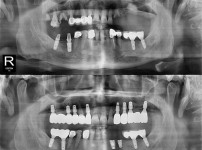

种植牙

全口种植牙